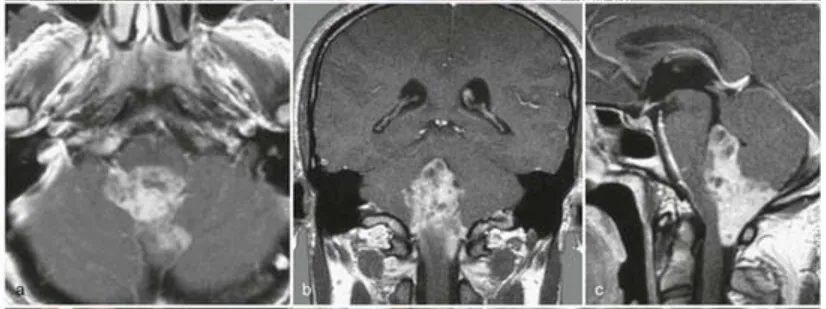

病例二:31岁男性患者

因颈部疼痛及步态共济失调就诊,术前MRI(a-c)显示第四脑室及背侧颅颈交界区存在巨大室管膜瘤。巴教授实施手术后,术后MRI(e)证实肿瘤全切,术后未出现新发神经功能缺损。